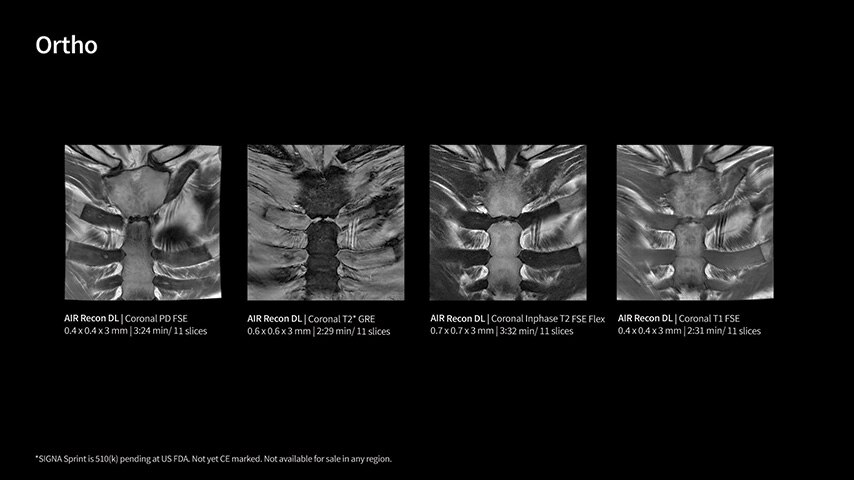

Imaging capabilities to unlock the power to explore further

High gradient performance

The growing clinical need within oncology and cardiology requires an MRI scanner that can rise to the challenge. With a high gradient performance of 65/200, SIGNA Sprint helps deliver crystal-clear imaging for ultimate diagnostic confidence. Improved signal-to-noise ratio (SNR) and diffusion, with deep-learning solutions that could enhance diagnostics and treatment response monitoring in your oncology patients.¹ Additionally, the shift from qualitative to quantitative cardiac MRI reduces the time and expertise needed to interpret scans and offers greater consistency and reliability. Helping you to unlock the power to explore further - even in your most challenging cases.

Deep-learning intelligence

Unlock your potential

With GE HealthCare's comprehensive suite of deep-learning solutions integrated into SIGNA Sprint, you can unlock the full potential of your MRI system. No need for complicated patient setups or imaging protocols. The exceptional intelligence of our AI solutions offer multiple benefits, with AIR Recon DL giving pin-sharp images, Sonic DL accelerating scans up to 12x, and AIR x enabling automated slice placement. All helping to enhance your department’s workflow efficiency, increase patient throughput, and get the diagnostic clarity you need, faster.¹ Meaning you can spend more time on what truly matters—personalized patient care, enabling optimized treatment plans and treatment response monitoring—ultimately, supporting better clinical outcomes.